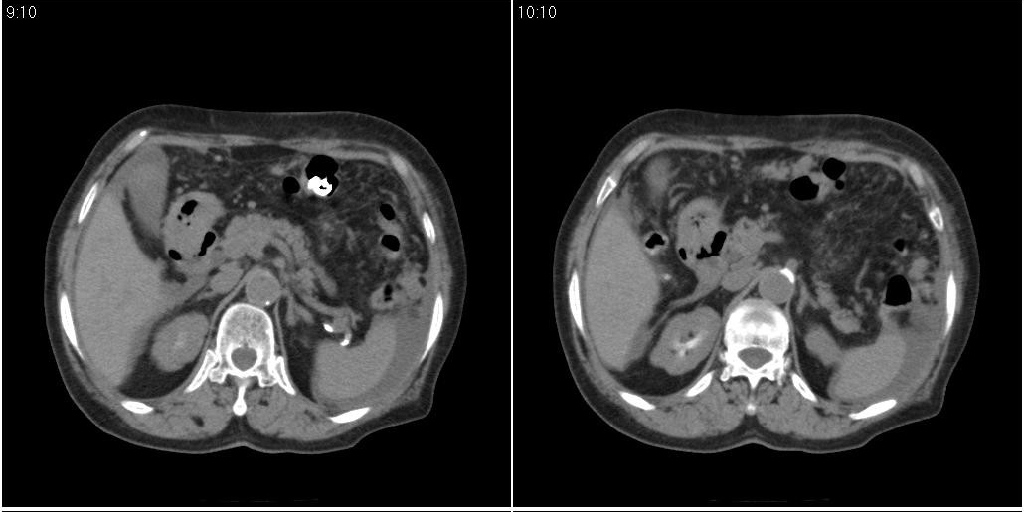

支持!另腹腔少量积液。

胆囊炎,胆结石,胆囊窝积液,胸腹水。

胆囊内稍高密度影,无强化,胆囊壁增厚,周围见低密度影,右侧膈肌角及脾周水样密度,支持胆囊泥沙样结石,胆囊炎、胆囊窝积液,胸腹水。